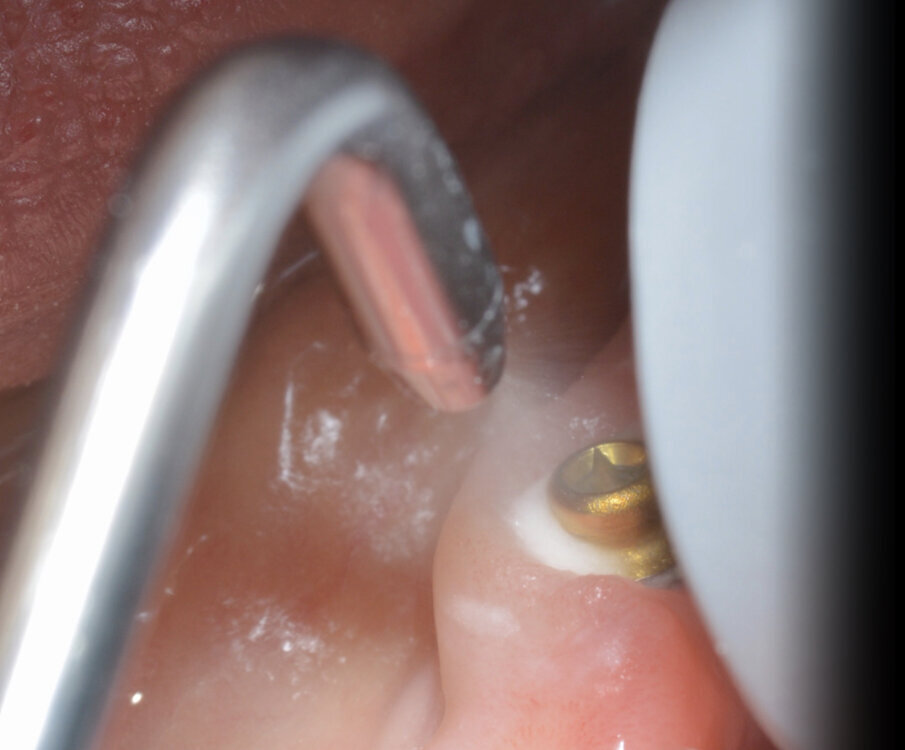

In particolare le polveri di glicina grazie al loro elevato potere antimicrobico e alla loro granulometria ridottissima, permettono un’accurata disinfezione a livello sopra e sub gengivale dell’intero cavo orale, soprattutto a livello del tragitto trasmucoso dell’abutment. In foto possiamo vedere un OT Equator (Rhein83, Italia) utilizzato per protesi fissa con la sistematica OT Bridge (Rhein83, Italia) (Figg. 5, 6). La rimozione totale del Biofilm batterico a livello sopra e sotto gengivale permette una “restitutio ad integrum” del tessuto gengivale, con una disinfezione profonda a livello tissutale.

Fig. 5_Manovre di air polishing su OT Bridge.

Fig. 6_Manovre di rimozione del biofilm batterico su OT Equator.

Per procedure di igiene in presenza di tartaro sono nati inserti in peek in modo da preservare sia i tessuti molli e duri ma soprattutto i manufatti protesici in modo da evitare abrasioni o scalfitture (Figg. 9, 10).

Fig. 9_Punte ultrasoniche in Peek.

Fig. 10_Rimozione della placca con strumenti in Peek che non rovinano l’abutment.